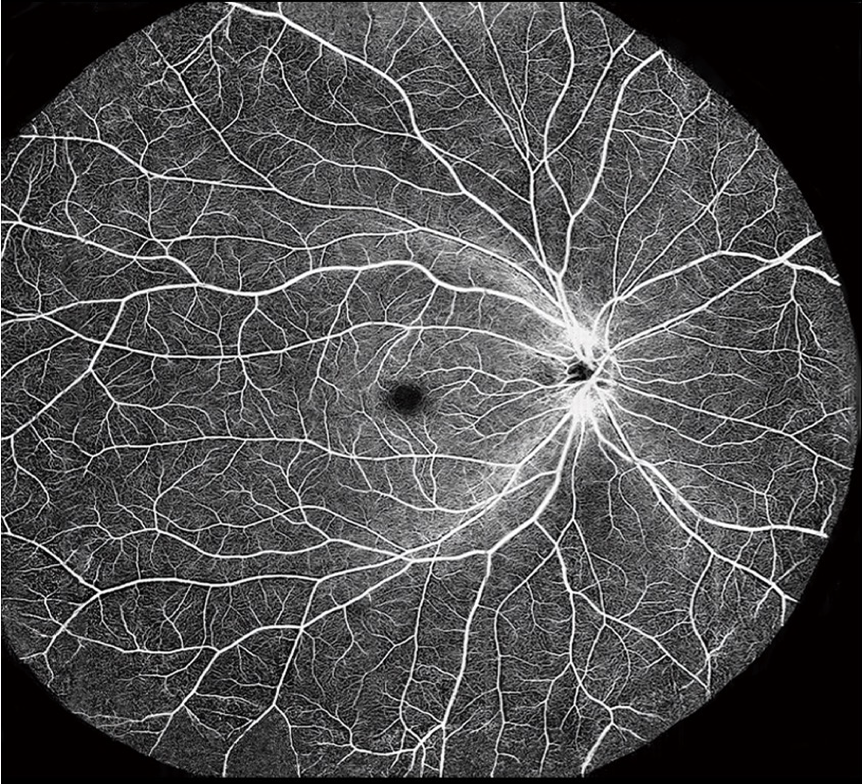

眼科智能OCTA,实现多病种筛查

【OCT痛难点】:价格昂贵、阅片门槛高、SD-OCT实现血流成像难度大

【首创优势】:在SD-OCT血流成像的技术基础上,首创OCT-AI辅助诊断功能,满足新兴市场要求

【OCT自动阅片】:数千张断层扫描图、血流成像图自动查找异常、病灶识别、诊断分析

【辅助诊断】:八大类、五十余种眼病、心脑血管疾病等数秒内出具结果,极大提升效率